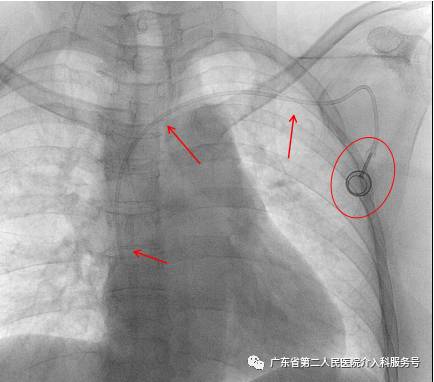

D.埋好输液港(红圈内)后,可透视了解和捋顺导管,防止导管打折,以及导管远端在下腔静脉内的深度(常为T5~T7之间)